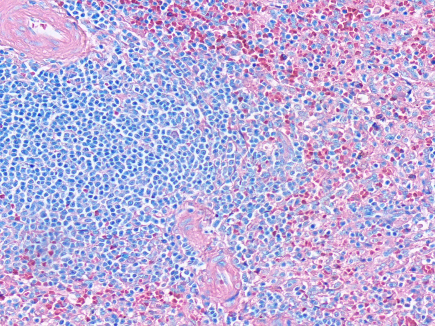

Staining method for different kind of cells in blood and bone marrow smears.

For staining in hematology, cytology and staining sections of hematopoietic organs in histopathology.